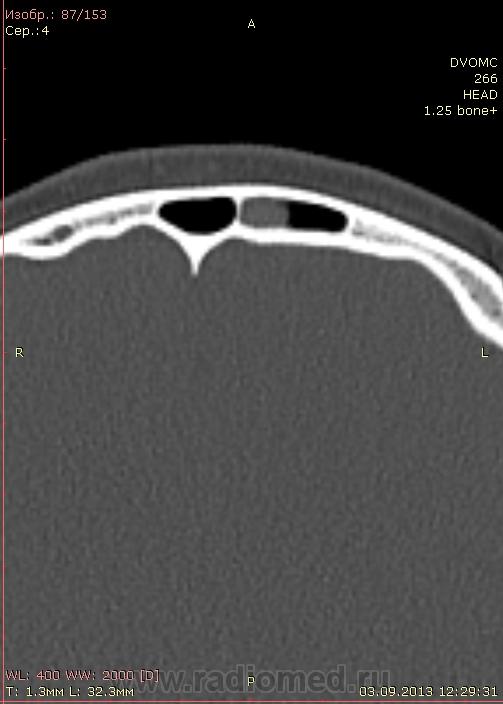

КТ головного мозга. Выстрел в лоб. В упор.

Дувушка 19 лет. В направлении огнестрельное ранение лобной области(пневматический пистолет). Металлический шарик вытащили из под кожи. Отправили на КТ и наблюдение в поликлинику. Из жалоб небольшое головокружение, головная боль. DICOM здесь http://files.mail.ru/F25AE2CF07AB4813BF046CE33FB20034

Кости вроде целы, мозги тоже ничего?

Похоже что это кровь свернувшаяся в лобной пазухе?

А не плотновата для кисты? С учетом травмы...?

Этмоидит слева (передние решетки), утолщение слизистой в левой в/ч пазухе. И полип верхней стенки левой лобной пазухи. Это не кровь, плотность 110 ед.Н и выше при большом увеличении. По дайкомам травматических изменений нет.